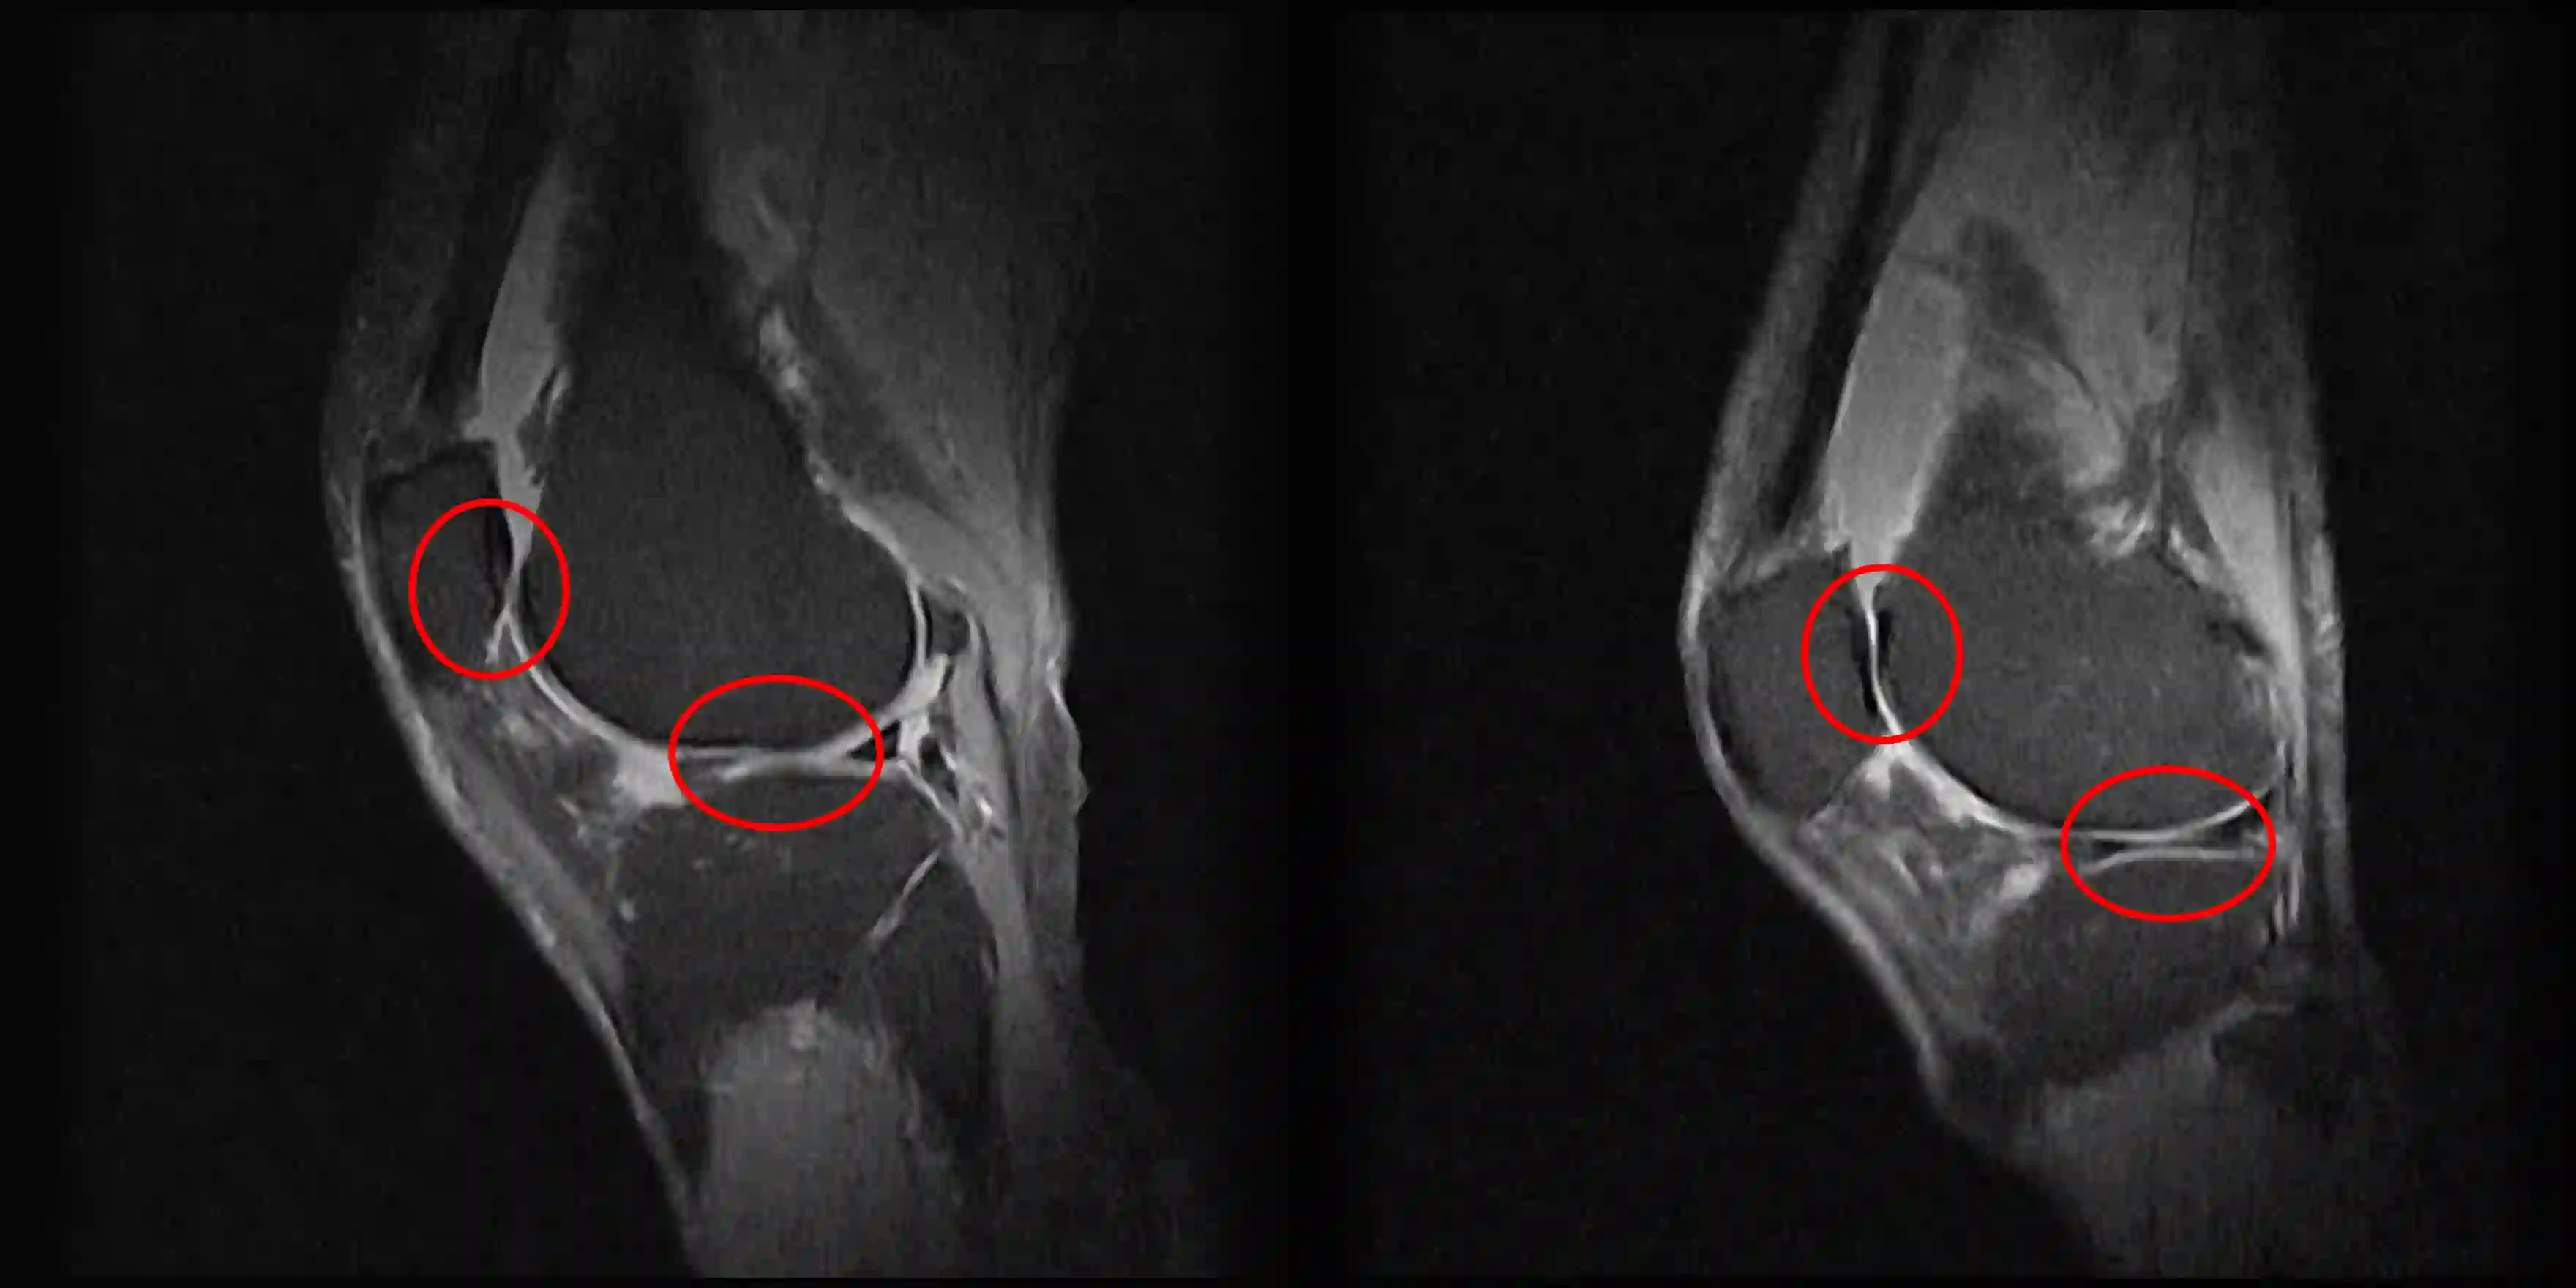

In recent years the NHS has been having increased difficulty seeing all low-risk patients, this includes but not limited to suspected osteoarthritis (OA) patients. To help address the increased waiting lists and shortages of staff, we propose a novel method of automated biomarker identification for diagnosis of knee disorders and the monitoring of treatment progression. The proposed method allows for the measurement and analysis of biomechanics and analyse their clinical significance, in both a cheap and sensitive alternative to the currently available commercial alternatives. These methods and results validate the capabilities of standard RGB cameras in clinical environments to capture motion and show that when compared to alternatives such as depth cameras there is a comparable accuracy in the clinical environment. Biomarker identification using Principal Component Analysis (PCA) allows the reduction of the dimensionality to produce the most representative features from motion data, these new biomarkers can then be used to assess the success of treatment and track the progress of rehabilitation. This was validated by applying these techniques on a case study utilising the exploratory use of local anaesthetic applied on knee pain, this allows these new representative biomarkers to be validated as statistically significant (p-value < 0.05).